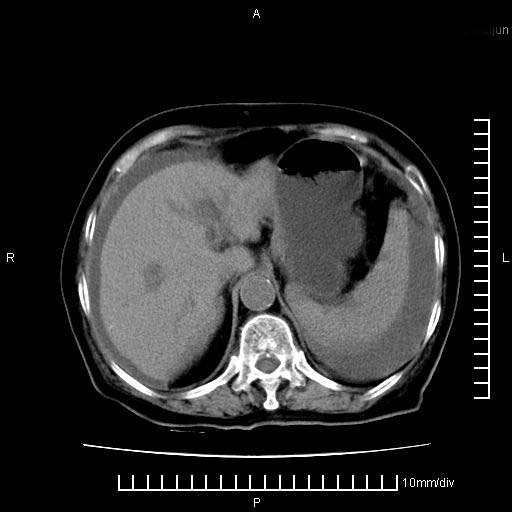

上腹疼痛月余,外院核磁诊断胰腺癌。现临床示右下腹可明显触及包块,可片子上怎么没有看到?

1.胰腺颈体部癌。

2。腹腔积液。

3。右胸腔积液,伴右肺下叶部分萎陷。

1。胰腺ca伴腹膜腔转移

2。肝左叶低密度灶,考虑转移可能

胰腺结构模糊,胰尾部见囊性包块,周围脂肪密度增高,左肾前筋膜增厚,胸水、腹水。不符合胰腺ca伴腹膜腔转移。考虑胰腺炎伴假性囊肿形成、胸腹腔积液。

1、考虑胰腺癌伴腹膜腔转移,胸腹水。

2、肝脏转移可能。

1)考虑胰腺癌并胰腺假性囊肿形成。2)肝内低密度灶,不排除转移。3)右肾盂积水。4)腹水。5)右侧胸腔积液并右肺下叶部分膨胀不全。

考虑胰腺ca伴腹膜腔转移、肝左叶转移、右肾积水。右胸腔积液。